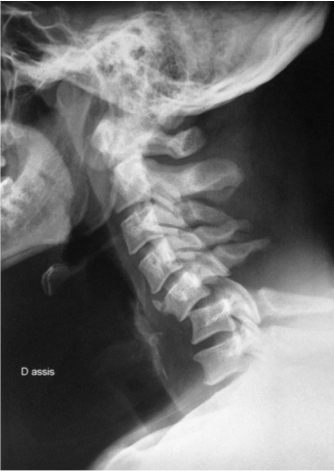

Fracture Instable Bi Isthmique De C2 Avec Hematome Epidural

An Unusual Hangman S Fracture Description And Surgical Management Sciencedirect